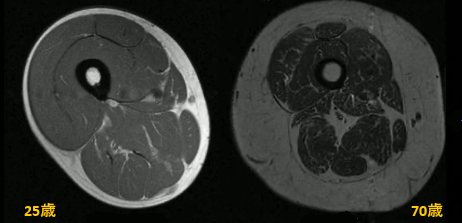

加齢に伴う筋肉量の推移

加齢に伴い、筋肉量は著しく低下、萎縮するだけでなく、筋肉の質の低下、骨量の低下が起こり、死亡リスクも上昇します。